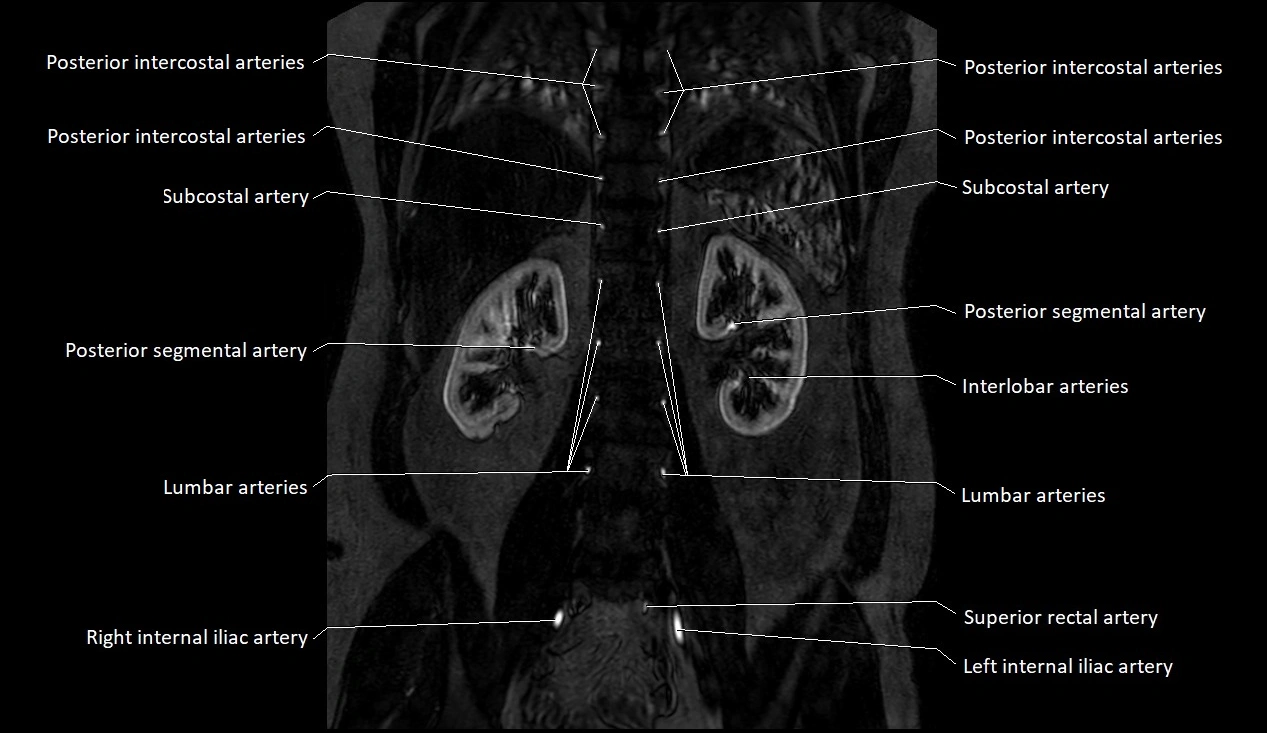

MRI images

image